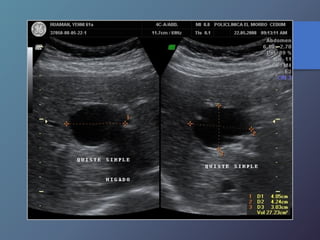

Quistes Simples

Características Ecográficas

• Imágenes anecoicas.

• Pared fina bien delimitada.

• Reforzamiento posterior.

Quistes Simples Características Ecográficas •Imágenes anecoicas. • Pared fina bien delimitada. • Reforzamiento posterior.